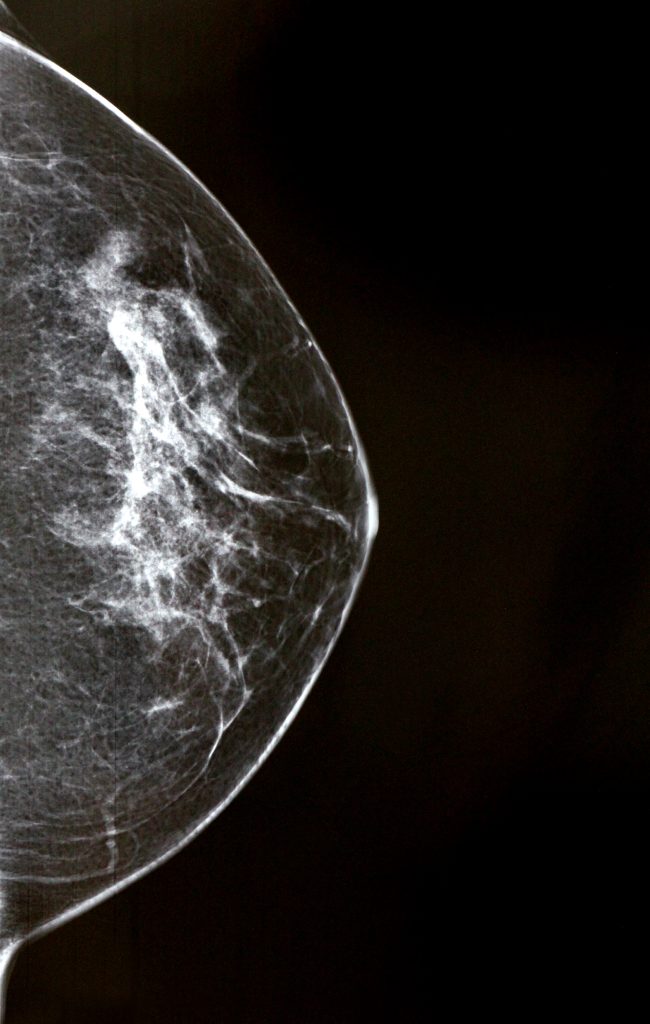

What is a mammogram?

A mammogram is an X-ray picture of the breast. Doctors use a mammogram to look for early signs of breast cancer.

Some women might feel discomfort during the procedure as the breasts are compressed for a few seconds. However, the discomfort is temporary and is necessary for producing clear images.

Herscan is a state-of-the-art ultrasound screening for the breasts. It is designed to complement traditional mammography by providing a more detailed, nuanced look at the breast tissue, particularly in women with dense breast tissue.

While mammograms use X-rays to image the breast tissue, Herscan uses high-frequency sound waves. This allows it to provide a different perspective and can be more effective in identifying abnormalities, particularly in denser breast tissue.